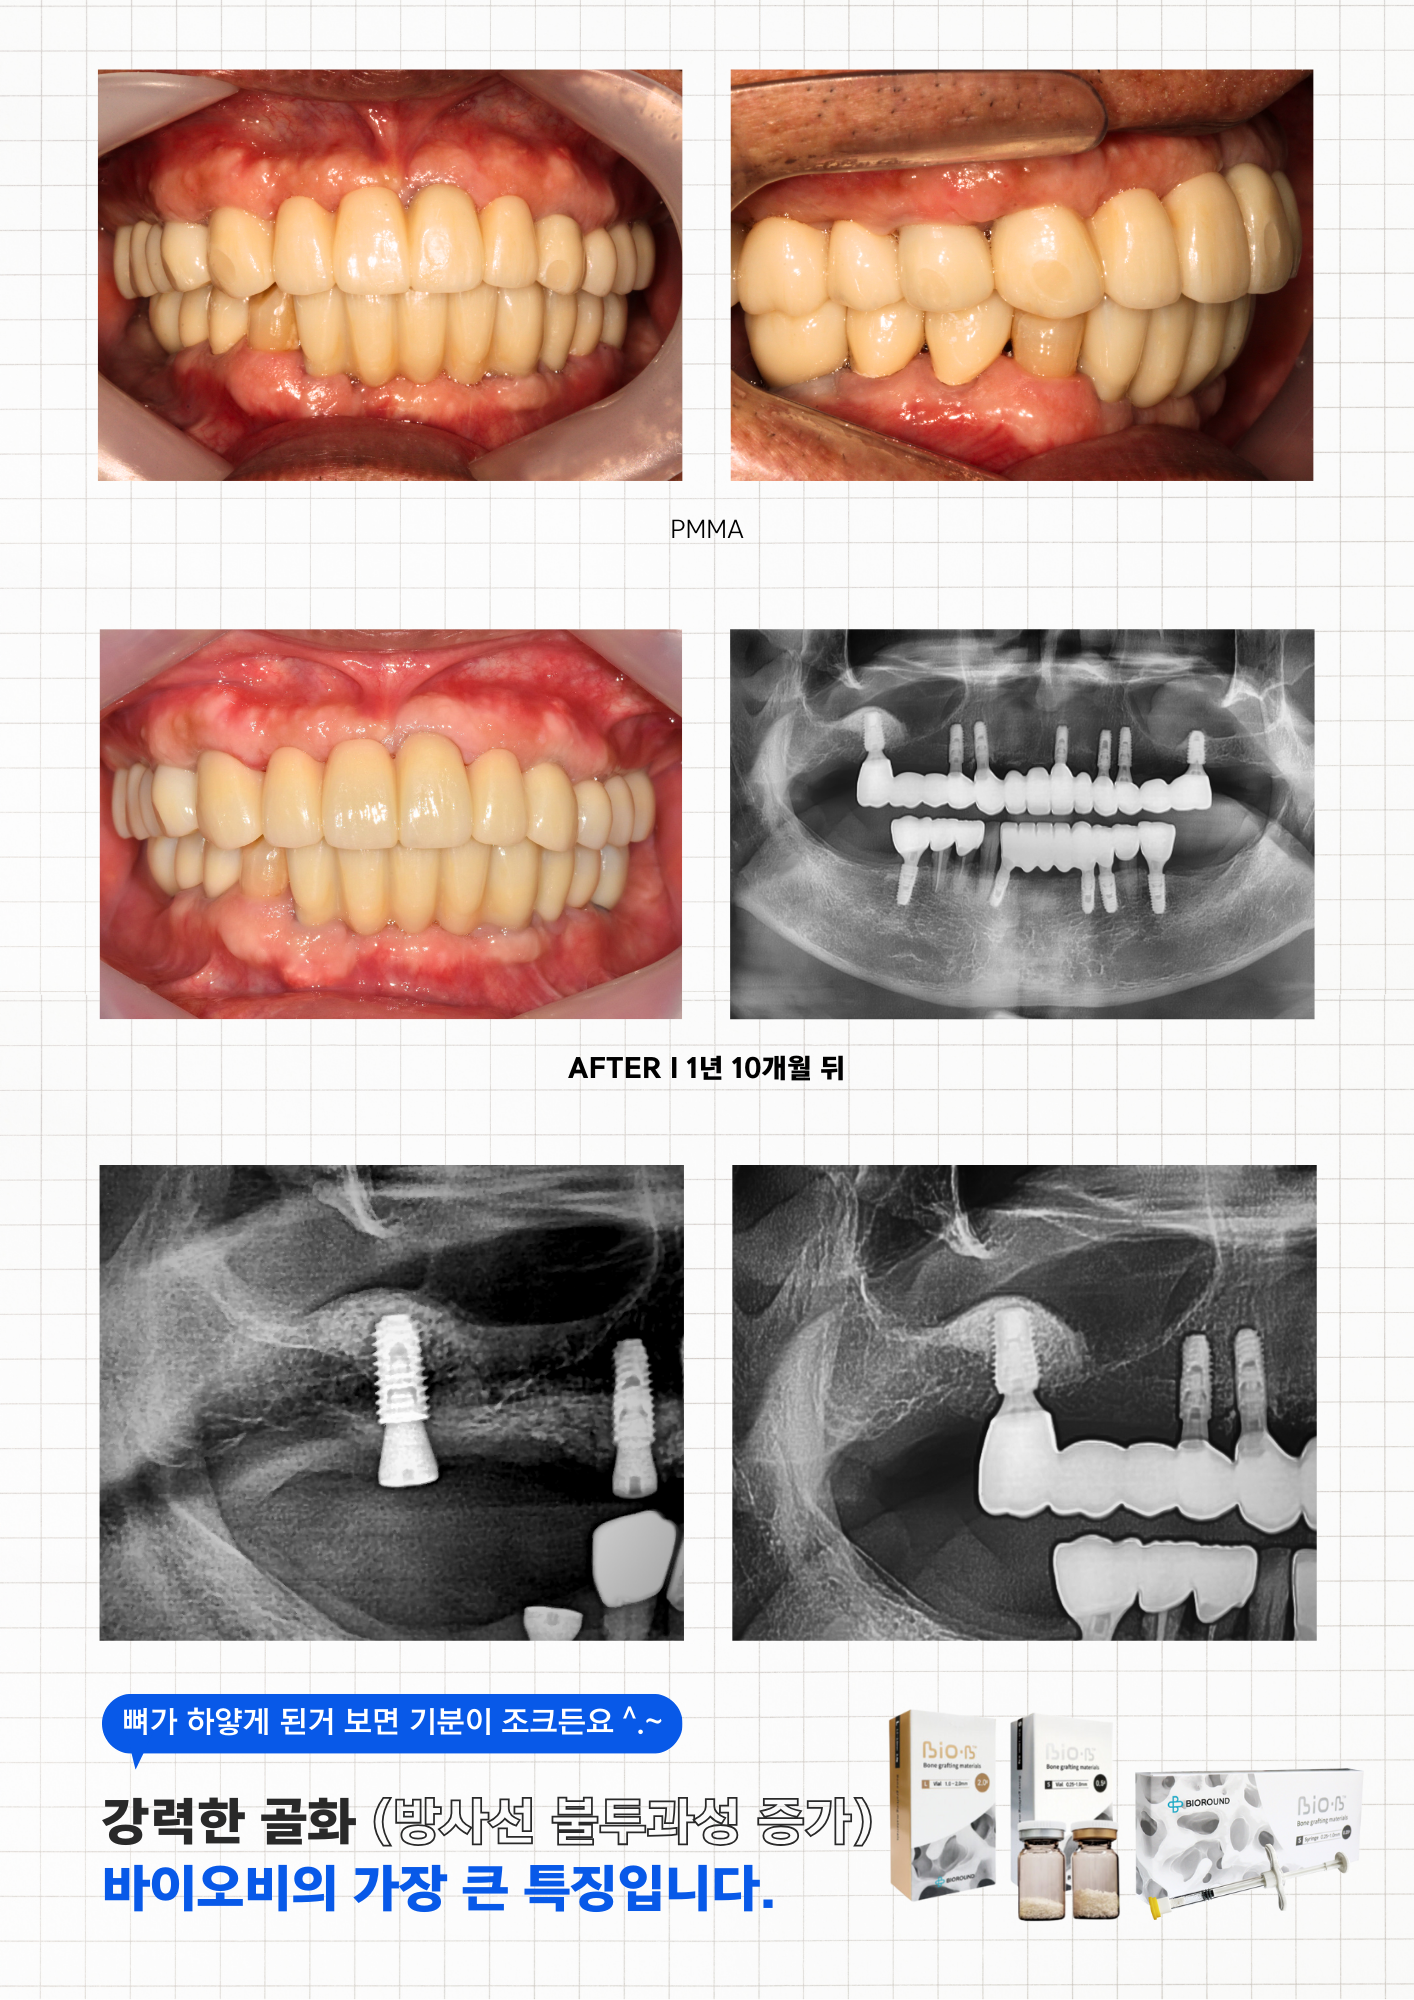

상품 이미지